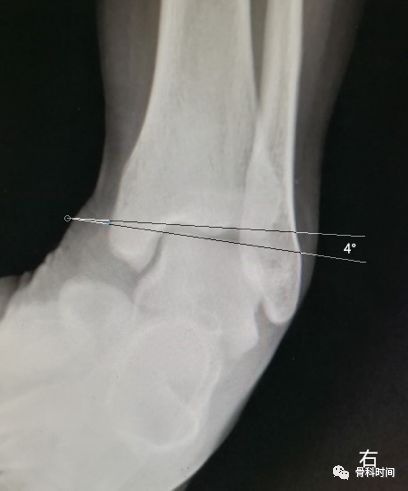

28 岁青年女性,约 2 年前左踝首次发生崴脚,未行外固定处理,近 1 年来左踝间断多次崴脚,双侧踝关节应力正位片测量距骨倾斜角,左侧为 10°,右侧 4°,左侧应力位状态下感疼痛,右侧无不适感,考虑左侧踝关节不稳。